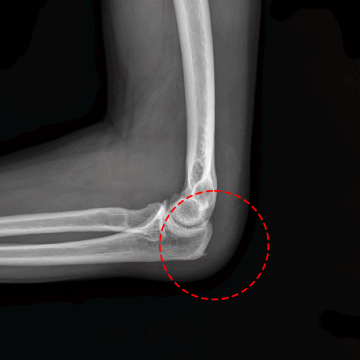

[수술 후 X-ray]

21년 10월 7일